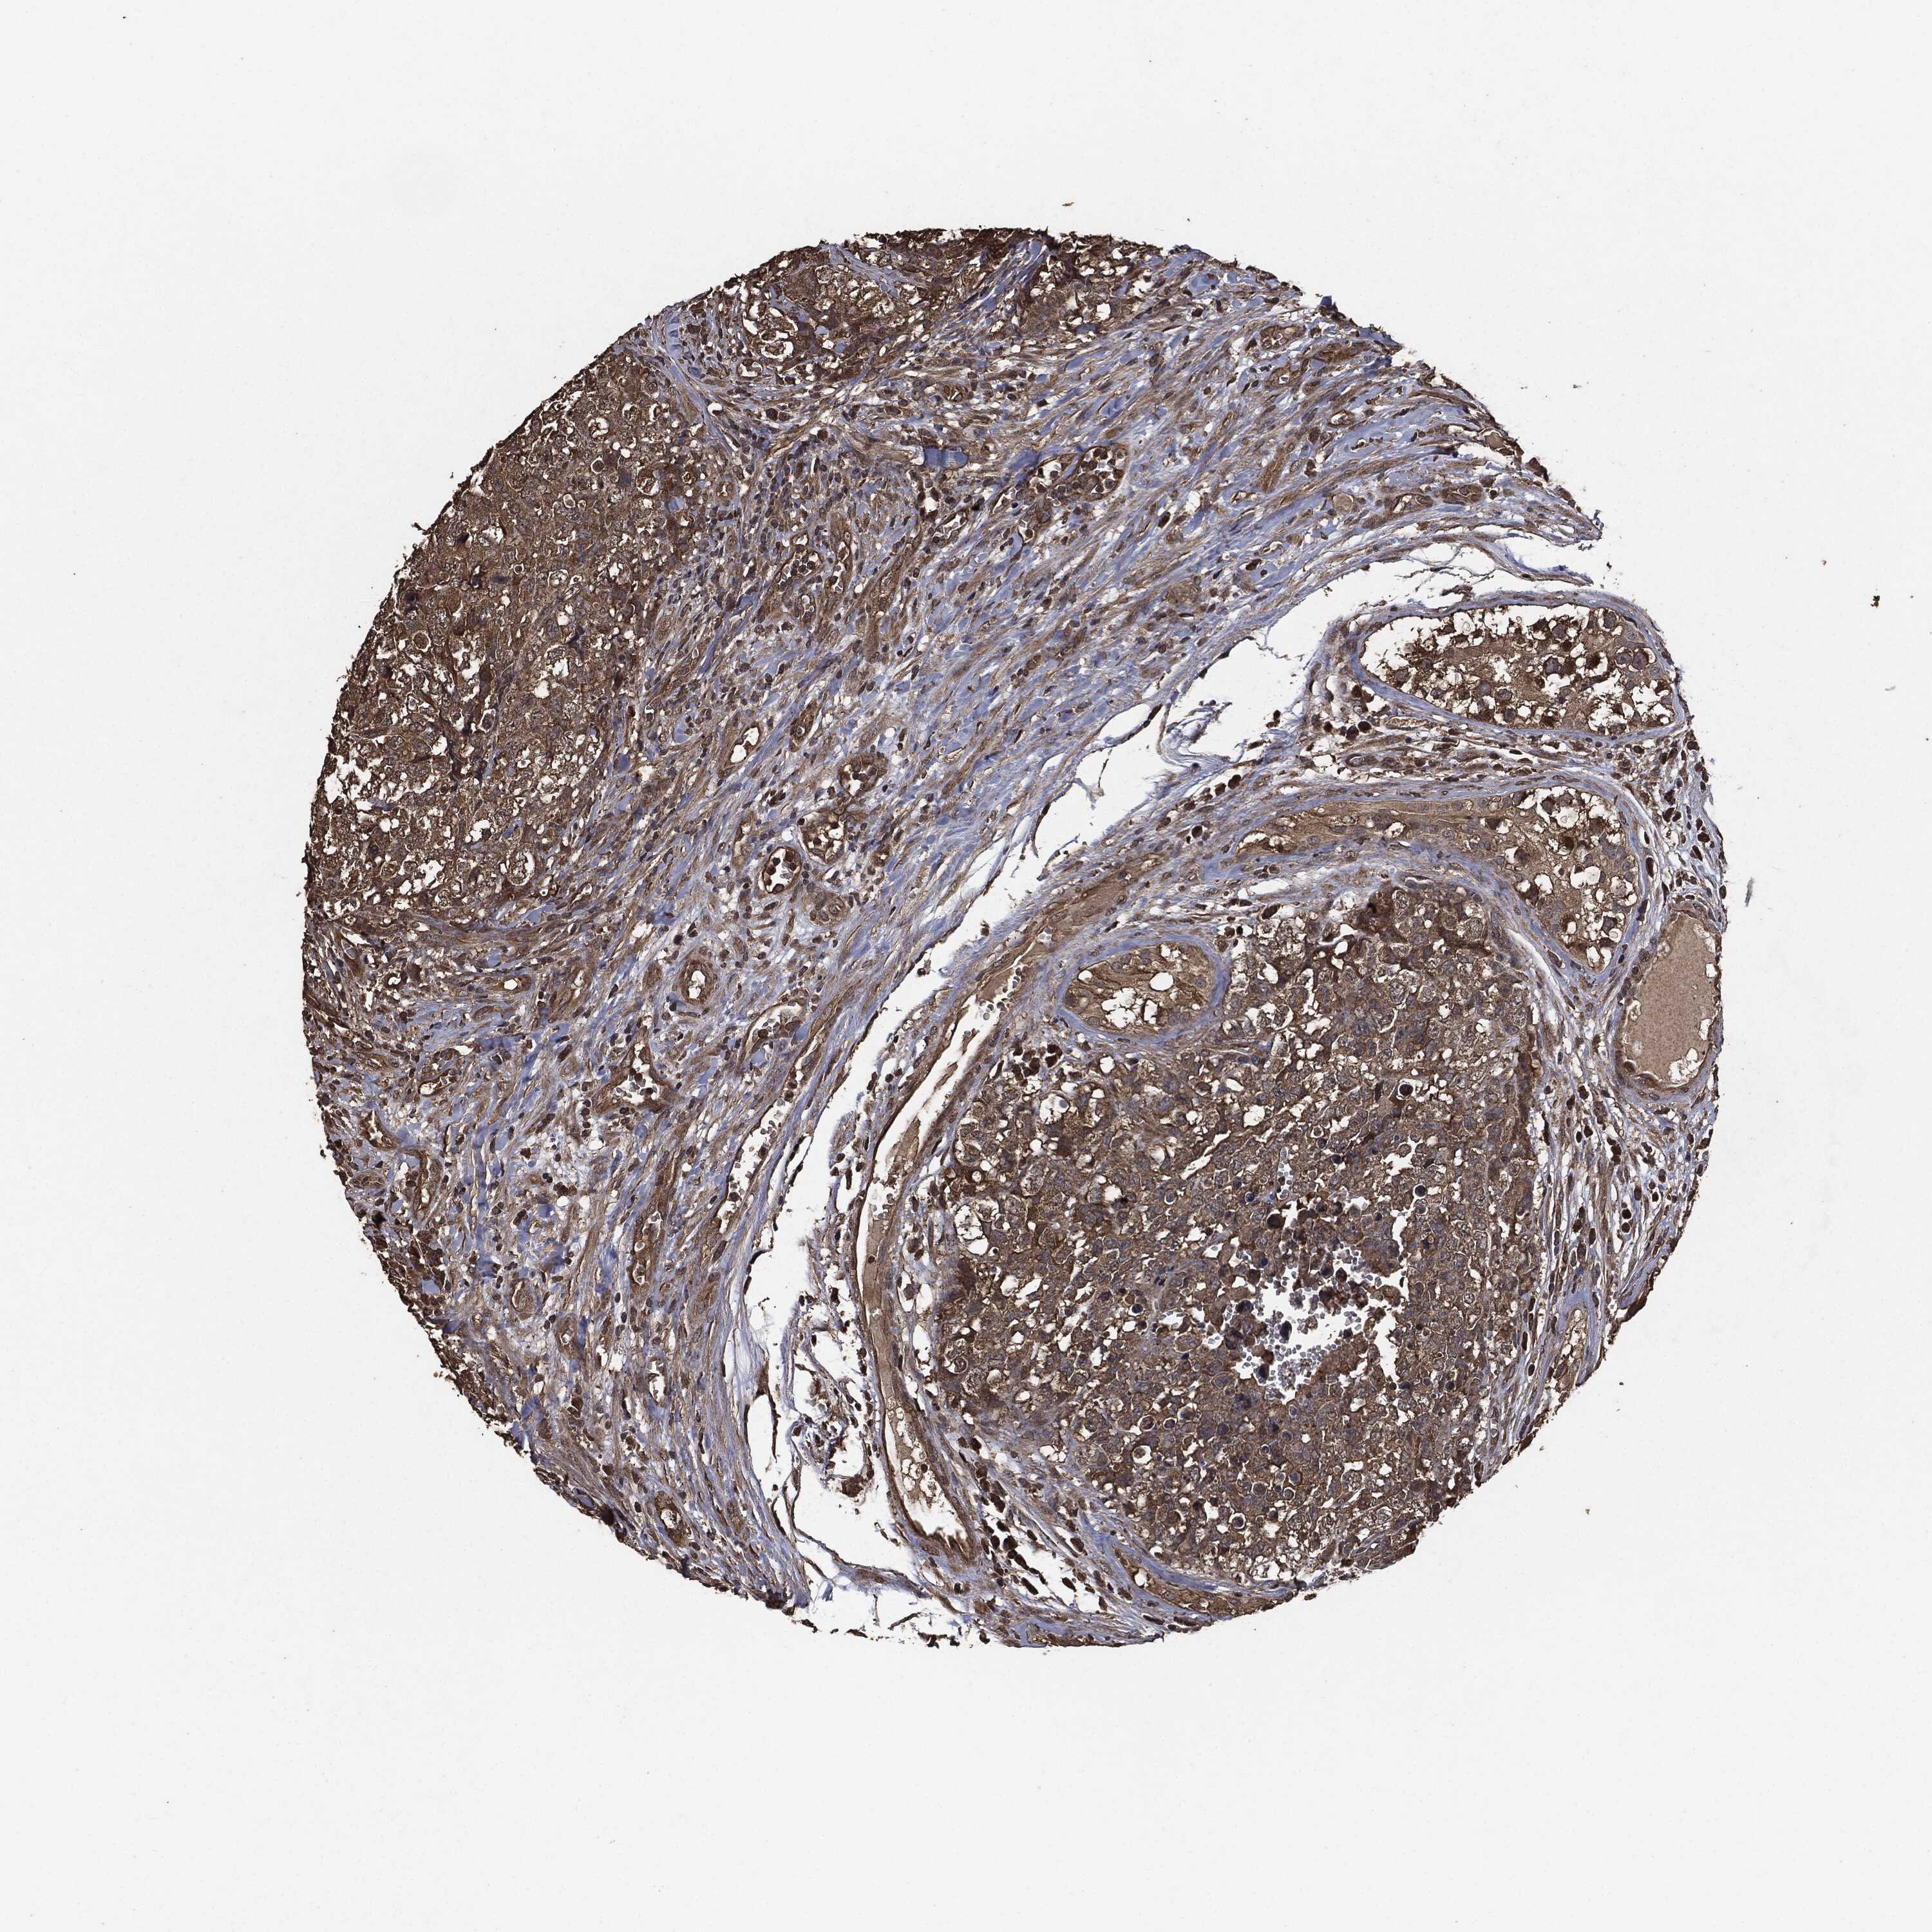

TESTIS CANCER - Protein expressioni

A mouse-over function shows sample information and annotation data. Click on an image to view it in a full screen mode. Samples can be filtered based on level of antibody staining by selecting one or several of the following categories: high, medium, low and not detected. The assay and annotation is described here.

Note that samples used for immunohistochemistry by the Human Protein Atlas do not correspond to samples in the TCGA dataset.

Antibody stainingi

Antibody staining in the annotated cell types in the current human tissue is reported as not detected, low, medium, or high, based on conventional immunohistochemistry profiling in selected tissues. This score is based on the combination of the staining intensity and fraction of stained cells.

Each image is clickable and will lead to virtual microscopy that enables deeper exploration of all samples and also displays staining intensity scores, fraction scores and subcellular localization as well as patient and tissue information for each sample.

Antibody HPA064427

Antibody HPA075510

Antibody CAB021903

Seminoma, NOS